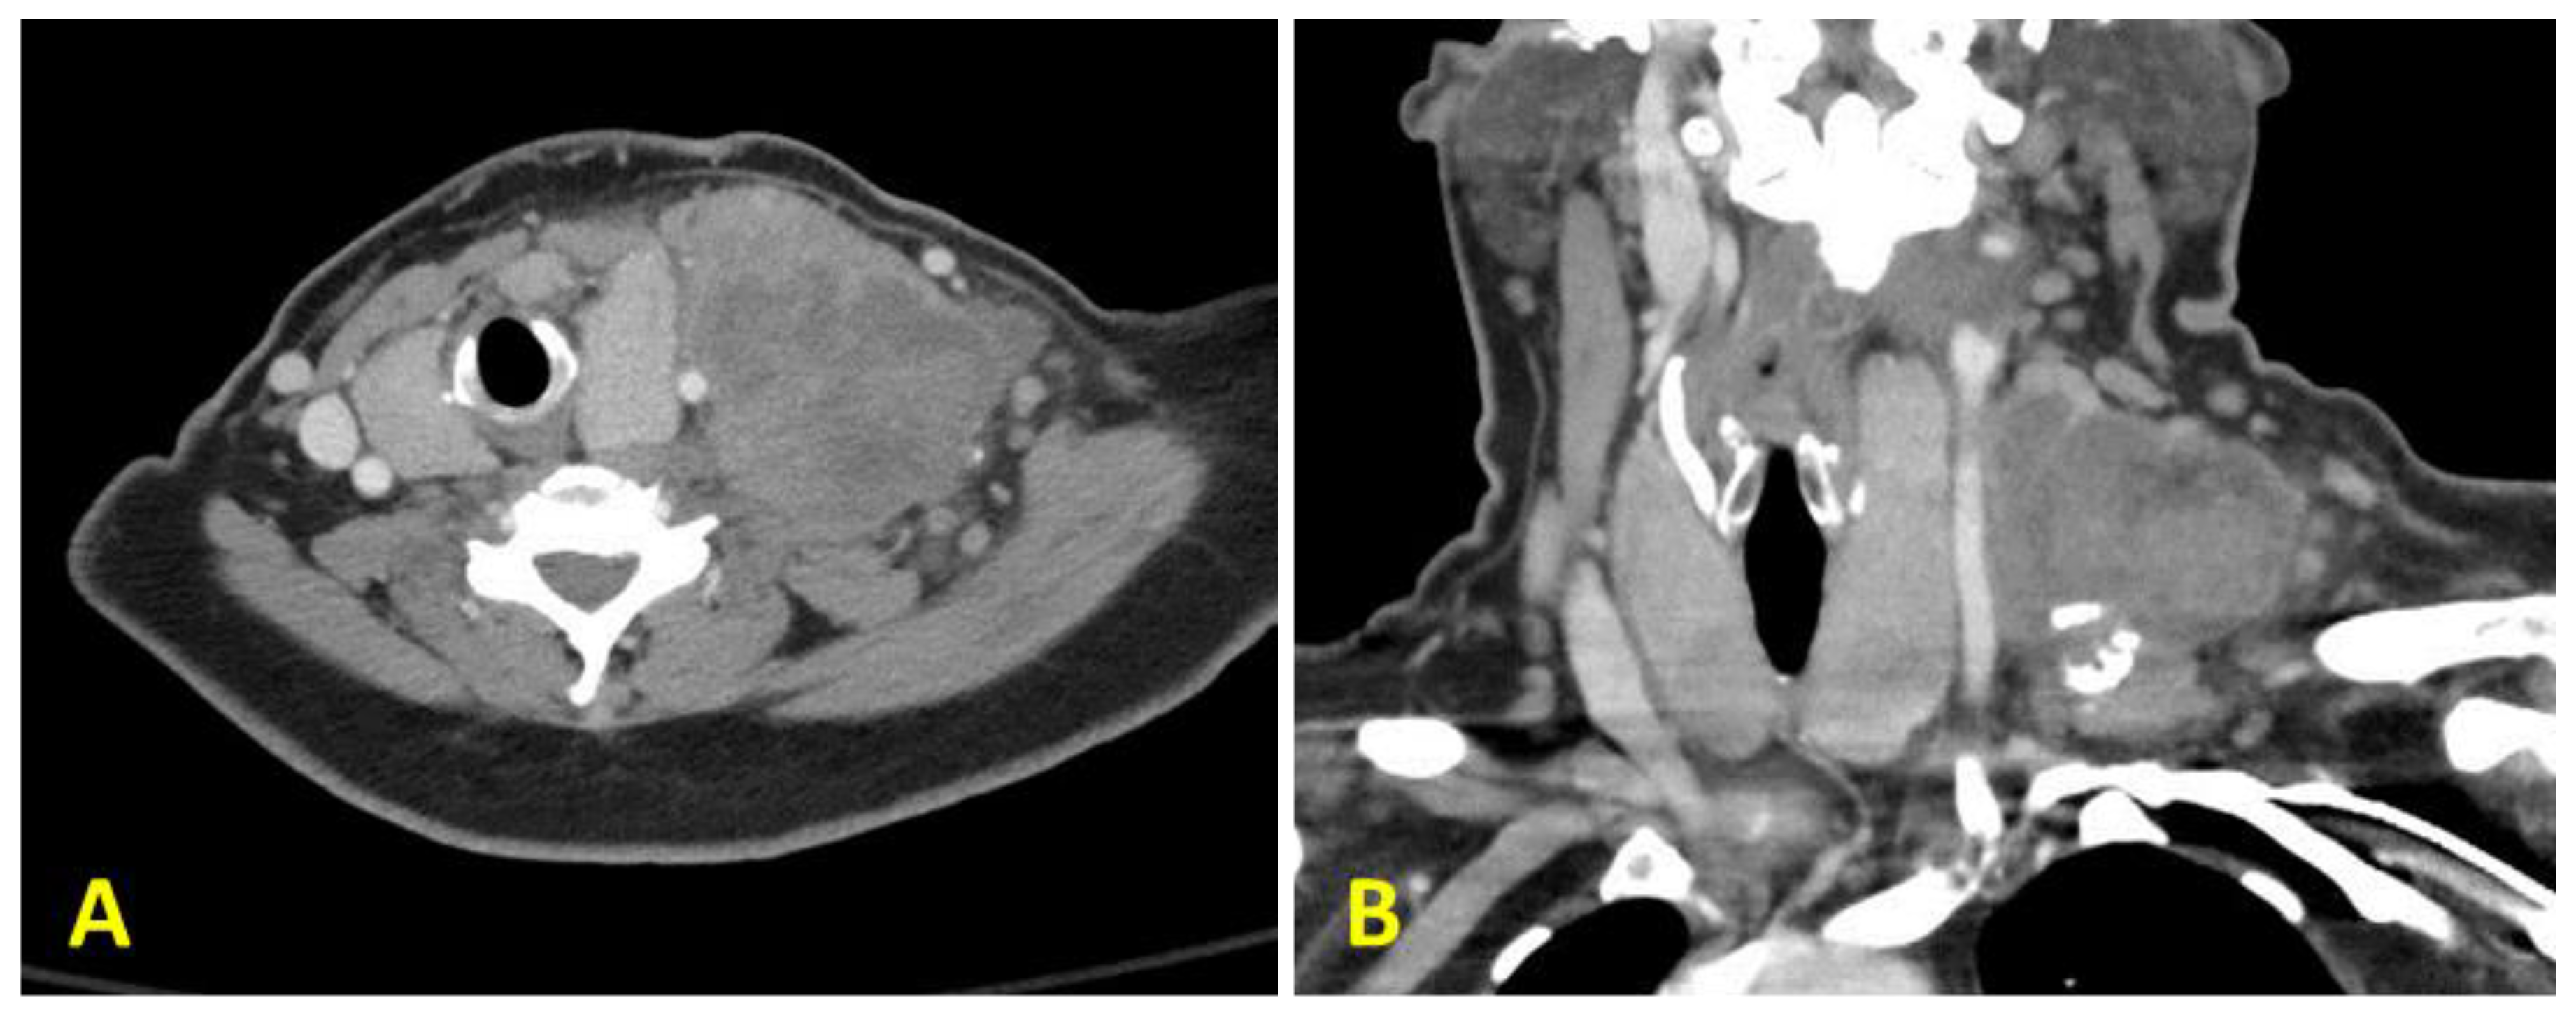

Figure 1.

Computed tomography (CT) scan of the patient’s neck showing a large mass located at the level 4, with central cystic necrosis ((A): cross section and (B): coronal section). Axial section (C) and coronal section (D) taken from a CT angiogram of the chest showing metastatic lung lesions.